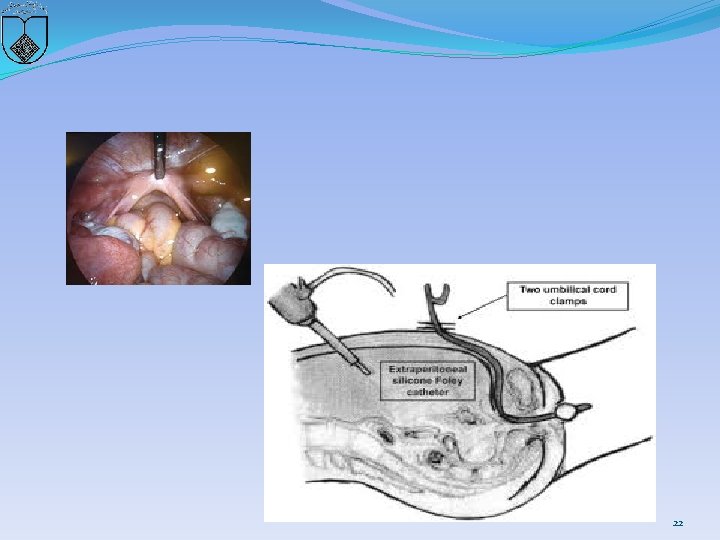

22

After instillation of a vasoconstrictive agent, the vesico-rectal septum is dissected with monopolar scissors down to a pseudohymenal membrane under constant visualization of the bladder and the rectum 23